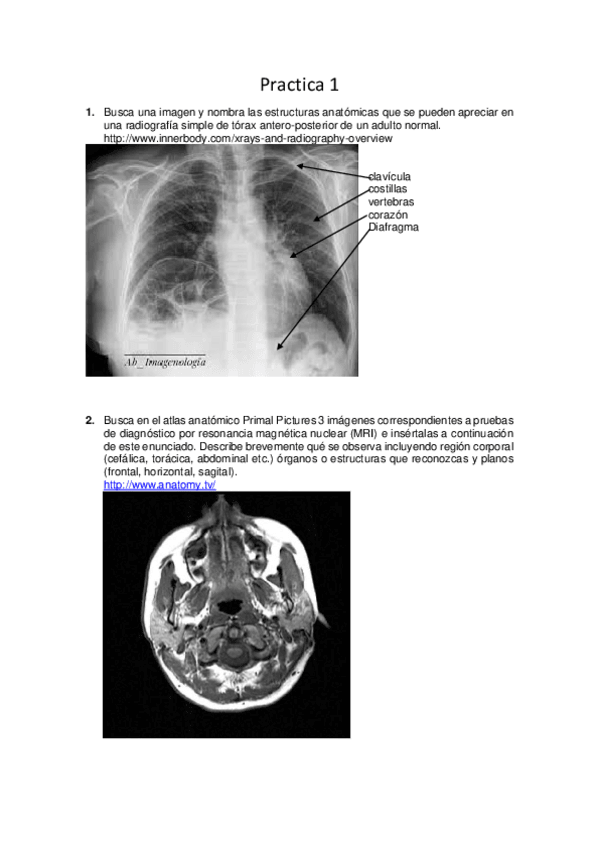

Practica-1-lab-Anatomia.pdf